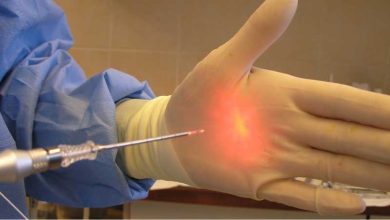

مرحله سوم: انجام درمان ریشه با ابزارهای مدرن